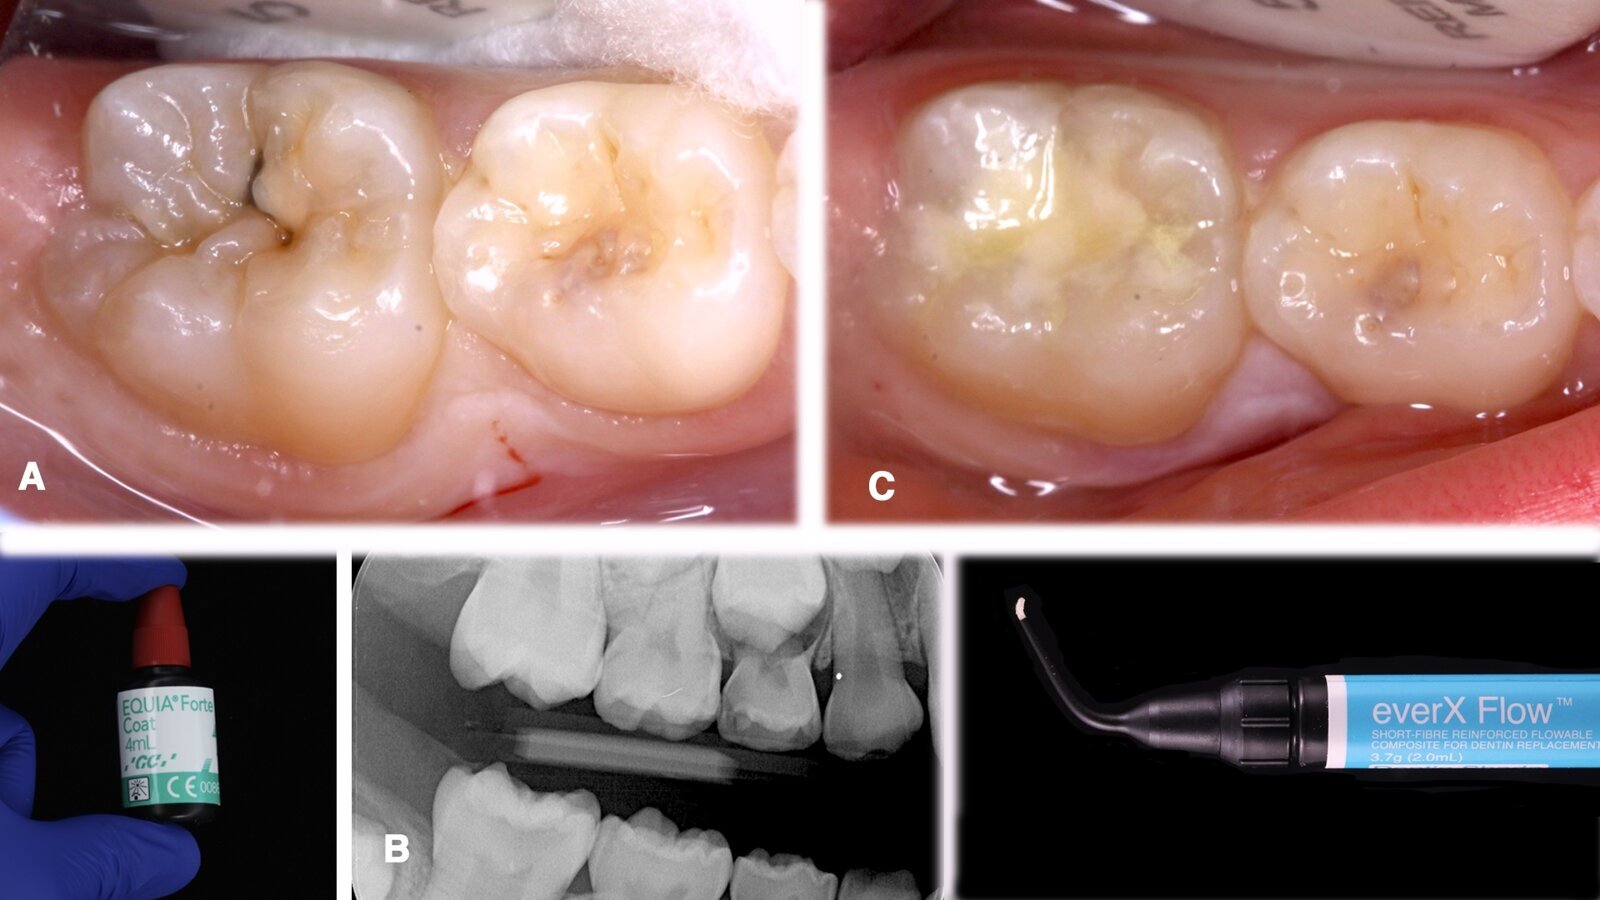

Imágenes inicial (A), radiográfica (B) y final (C) del diente 46 de una paciente de 7 años con sensibilidad dentinaria, que se restauró utilizando el material estético de fraguado rápido EQUIA Forte fil, y la resina compuesta everX Flow. Estos materiales utilizan la nueva tecnología de vidrio híbrido y actúan de forma sinérgica para formar un material más fuerte de colocación en bloque.

A continuación se presentan dos casos clínicos donde se aplican materiales a base de vidrios híbridos en un diente permanente joven con una lesión de caries primaria; en el segundo caso se utiliza resina reforzada por fibra como sustituto dentinario en un diente tratado endodónticamente.

Caso A

Paciente femenina de 7 años de edad se presenta en el consultorio por manifestar sensibilidad en el cuarto cuadrante al consumir bebidas o alimentos fríos.

Caso B

Paciente femenina de 64 años de edad se presenta al consultorio con una lesión de caries secundaria alrededor de una restauración con resina en las superficies oclusal y distal en un diente tratado endodónticamente (Fig. 14): el primer premolar superior izquierdo (diente 24).